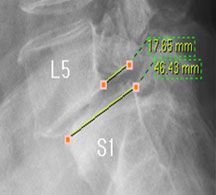

모커리한방병원 구○○ (50, 여) 척추전방전위증 2단계 실제치료사례 이미지

구○○ (50, 여) 척추전방전위증 2단계 입원치료기간 : 17일

입원시 퇴원시

허리 통증지수(NRS) 5 1

엉덩이 통증지수(NRS) 7 1

통증없이 걷는거리(m) 80m(하루 1회) 160m(하루 수회)